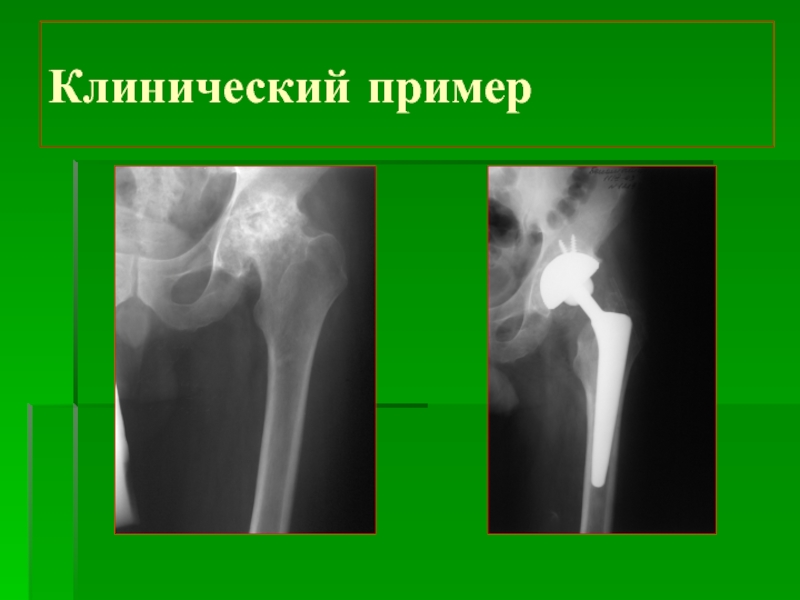

Слайд 5Клинический пример:

Диагноз:

Нестабильность эндопротеза

Клинический пример:Диагноз: Нестабильность эндопротеза